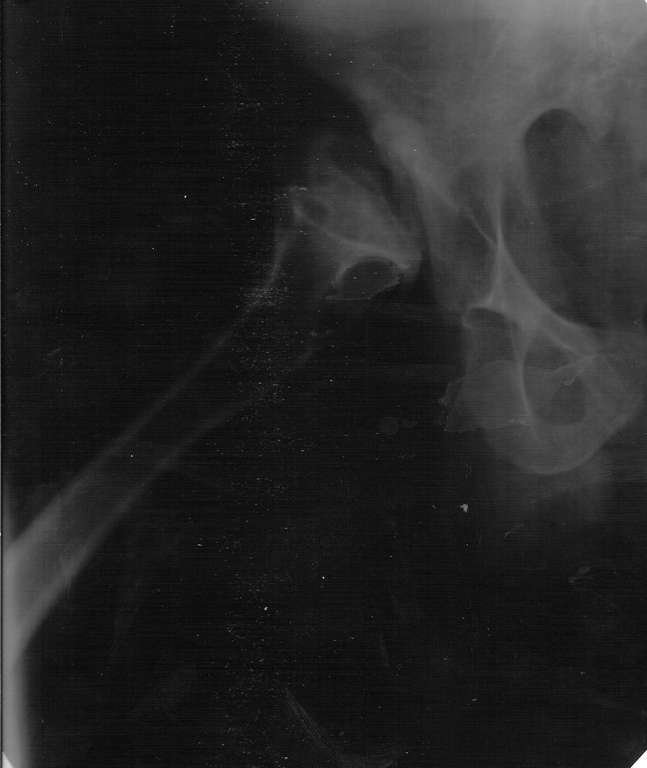

Прямая проекция т/б суставов

Алексей, судя по снимкам, правый тазобедренный сустав нуждается в замене. Думаю, что получится поставить протез без дополнительных конструкций во впадину и особых ножек. Важным является диаметр канала. Надо по шаблонам оценить размер. Самые маленькие из известных мне ножек в России предсталены у De Puy (бесцементная 6), и новинка от BIOMET бесцементная диспластическая ножка.